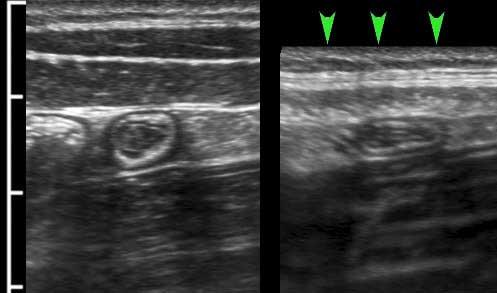

Lớp mỏng này (đầu mũi tên) tăng âm trên siêu âm và có thể thấy ở ruột non của bệnh nhân gầy.

Lớp cơ dọc chỉ giới hạn ở ba dải định hướng dọc, được gọi là dải cơ dọc kết tràng (teniae coli). Trong đại tràng rỗng, xẹp ở những bệnh nhân gầy, ba dải cơ dọc này (đầu mũi tên) thường có thể được xác định bằng siêu âm như một vùng dày lên cục bộ của lớp cơ, tách biệt với lớp cơ vòng bởi một đường tăng âm mỏng.

Trong hình ảnh theo chiều dọc này, chỉ xác định được một dải cơ dọc (đầu mũi tên).